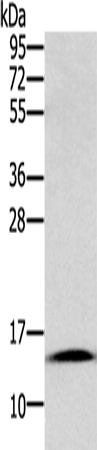

分类: 科研抗体货号: P08183别名: COT应用: WB,IHC反应种属: Human, Mouse, Rat